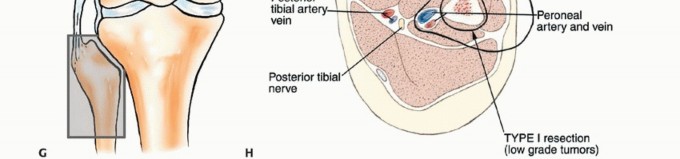

أنواع الاستئصال الجراحي للشظية القريبة

هناك ثلاثة أنواع رئيسية من استئصال الأورام حول الشظية القريبة:

-

الكشط (Curettage):

- الإشارة: يُستخدم للأورام الحميدة العدوانية والأورام الغرنية منخفضة الدرجة المرتبطة بتدمير قشري بسيط وامتداد خارج العظم ضئيل.

- الإجراء: يتم إزالة الورم يدويًا بواسطة مكشطة، ثم تُستخدم مثقاب عالي السرعة لتنظيف جدران تجويف الورم بدقة لضمان إزالة أي مرض مجهري متبقي.

- الحفاظ: يتم الحفاظ على العصب الشظوي المشترك والأوعية الدموية.

-

الاستئصال من النوع الأول (Type I Resection):

- الإشارة: يُستخدم لعلاج الأورام الحميدة العدوانية والأورام الغرنية منخفضة الدرجة التي تسببت في تدمير قشري كبير للشظية القريبة.

- الإجراء: يشمل إزالة الشظية القريبة، وغلاف عضلي رقيق من جميع الأبعاد، وموقع ارتباط الرباط الجانبي الوحشي (LCL). يتم الحفاظ على العصب الشظوي المشترك وفروعه الحركية، ويتم استئصال المفصل الظنبوبي الشظوي داخل المفصل.

- الحفاظ: يتم الحفاظ على العصب الشظوي والشريان الظنبوبي الأمامي عادةً.

-

الاستئصال من النوع الثاني (Type II Resection):

- الإشارة: يُستخدم لعلاج الأورام الغرنية عالية الدرجة، والتي عادةً ما يكون لديها تدمير قشري كبير مع امتداد خارج العظم.

- الإجراء: يشمل إزالة الشظية القريبة والمفصل الظنبوبي الشظوي، والحجرات العضلية الأمامية والجانبية، والعصب الشظوي، والشريان الظنبوبي الأمامي بشكل كامل. يتطلب هذا النوع ربط الشريان الظنبوبي الأمامي وقد يتطلب أيضًا التضحية بالشريان الشظوي.

- الحفاظ: لا يتم الحفاظ على العصب الشظوي والشريان الظنبوبي الأمامي.

يوضح الجدول التالي الهياكل التشريحية التي يتم إزالتها مع أنواع الاستئصال المختلفة للشظية القريبة:

| نوع الجراحة | موقع ارتباط الرباط الجانبي الوحشي | الشريان الظنبوبي الأمامي | العصب الشظوي |

|---|---|---|---|

| الكشط | سليم | سليم | سليم |

| استئصال من النوع الأول | مُزال | سليم | سليم |

| استئصال من النوع الثاني | مُزال | مُزال | مُزال |